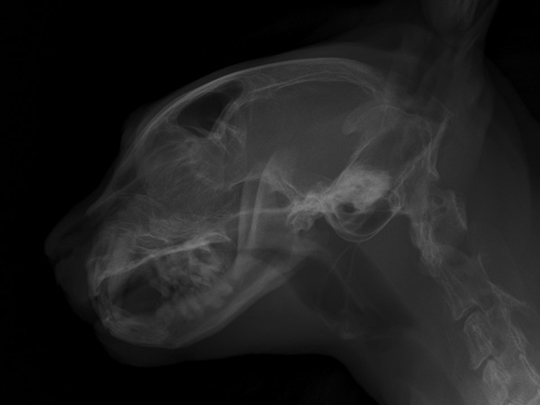

当院受診の3日前より、黄色い液体を5?6回連続で嘔吐し、その後より鼻出血および両側鼻腔の通気性低下が認められたとのことで、まず他院を受診されました。 その際に実施されたレントゲン検査では明らかな異常は認められなかったとのことです。 当院にて再度胸部および頭部のレントゲン検査を実施したところ、呼気時における咽喉頭部の一過性の拡張所見が認められましたが、骨の破壊などの明らかな構造的異常は確認されませんでした。 症状の急性発症であること、ならびに鼻閉および鼻出血を伴うことから、鼻腔・鼻咽頭内の異物の存在を強く疑い、同日にCT検査および内視鏡検査を実施しました。 検査の結果、鼻腔から鼻咽頭内にかけて毛玉と思われる異物を認めたため摘出を行ったところ、呼吸状態や全身状態は速やかに改善し、当日中に退院となりました。 その後の経過も良好で、現在までに1年が経過していますが、症状の再発は認められていません。

レントゲン画像で骨破壊等を評価

数日前に散歩後より急性の鼻炎症状および鼻出血が認められ、鼻腔内異物の存在を強く疑いました。 精査のためにレントゲン検査およびCT検査を実施し、鼻腔内異物および歯根膿瘍の疑いが示されました。 その後、鼻腔内視鏡を用いて異物の摘出および関連する抜歯を実施しました。